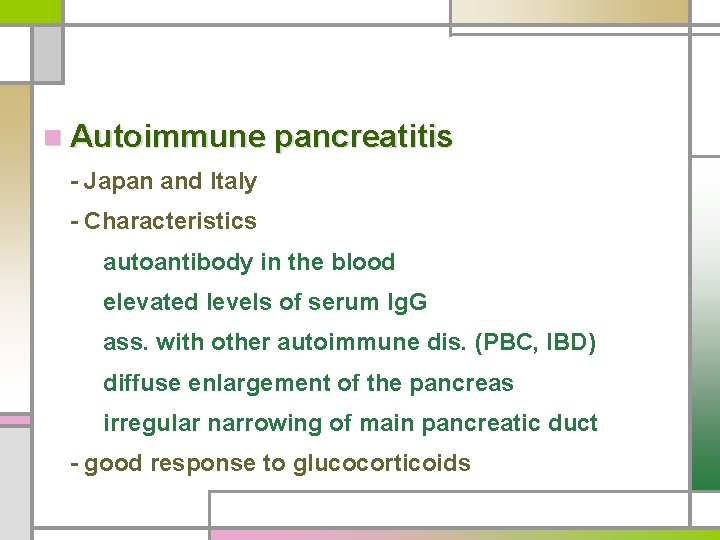

n Autoimmune pancreatitis - Japan and Italy - Characteristics autoantibody in the blood elevated levels of serum Ig. G ass. with other autoimmune dis. (PBC, IBD) diffuse enlargement of the pancreas irregular narrowing of main pancreatic duct - good response to glucocorticoids